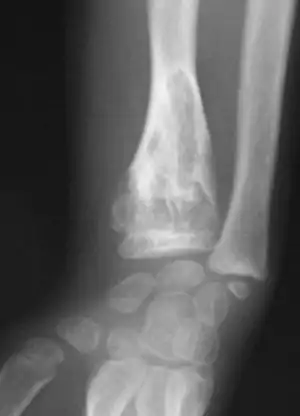

X-ray showing calcified enchondromas localized in finger a 37-year-old patient affected with Ollier disease

X-ray showing enchondromas localized in the humerus of a 37-year-old patient affected with Ollier disease

X-ray showing enchondromas localized in the lower part of the radius of a 37-year-old patient affected with Ollier disease

MRI showing enchondromas localized in the lower part of the radius of a 37-year-old patient affected with Ollier disease

MRI showing enchondromas localized in the lower part of the radius of a 37-year-old patient affected with Ollier disease.

Enchondromas localized in the upper part of the humerus of the same patient